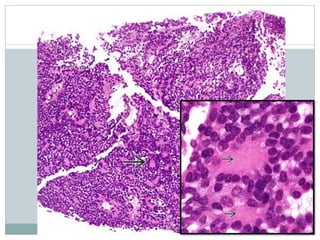

• #14 Some cases of ES feature conspicuous morphologic evidence of neuroectodermal differentiation in the form of scattered true rosettes . These tumors have also been described as primitive neuroectodermal tumors (PNETs). The true rosettes of ES (PNET) are formed by tumor cells arranged around a core of fibrillary material without formation of a central lumen. Cell boundaries are indistinct. These structures are also known as Homer Wright rosettes.

Cells  Uniform cells Rarely spindled  Scant cytoplasm with indistinct membranes  Clear from glycogen  Fine chromatin, inconspicuous nucleoli  Atypical (large cell) variant  Large nuclei, conspicuous nucleoli, pleomorphism, spindling

• #23 Nuclei in ES are generally small, round, and relatively uniform. Nucleoli are small, if present. Occasional cases show scattered cells with more prominent nucleoli.

• #24 An admixed population of degenerating tumor cells with smaller, hyperchromatic, and angulated nuclei may be seen in many cases of ES and have been referred to as "dark" cells. Note the contrast with the more conventional tumor cells .